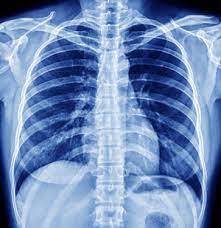

Enter Sanya's Digital X-Ray service, a revolutionary solution that promised to change the game for Priya and others like her. This service, nestled in the heart of Bhopal, offers a modern, efficient, and precise approach to diagnostic imaging. The digital X-ray technology provides high-resolution images with minimal radiation exposure, ensuring a safer and more comfortable experience for patients.

The most remarkable part of Priya's experience was the speed and clarity with which her results were delivered. The high-quality images captured by the digital X-ray revealed the underlying issue with precision, allowing her doctor to diagnose her condition accurately. This clarity not only facilitated a swift diagnosis but also paved the way for a targeted treatment plan that addressed her pain effectively.